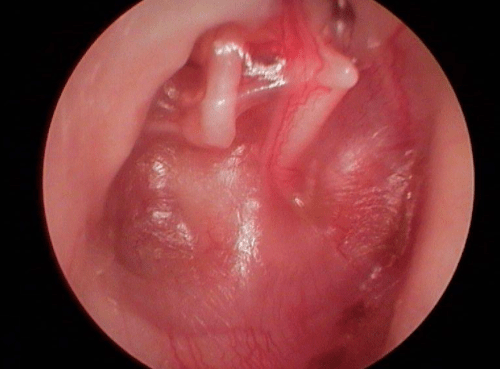

On distingue les OMC bénignes, ou non choléstéatomateuses, (otite séromuqueuse et otite moyenne chronique à tympan ouvert), qui peuvent laisser des séquelles tympaniques et ossiculaires accessibles au traitement chirurgical, et les OMC dangereuses ou choléstéatomateuses, qui n’ont aucune tendance à la guérison spontanée et peuvent entraîner des complications dont certaines mettent en jeu le pronostic vital.

- un écoulement purulent et parfois fétide de l’oreille malade ;

- l’examen de l’oreille, pour vérifier l’état du tympan ;